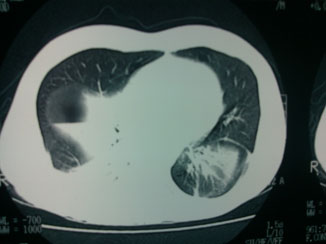

La tele de tórax mostró un hemidiafragma derecho elevado con nivel hidroaéreo, por lo que hubo sospecha de absceso pulmonar (figuras 3 y 4). Por lo tanto, se llevó a cabo una TAC de tórax en la que se observó una imagen redondeada con doble nivel hidroaéreo de aspecto tabicado, condensación basal derecha y derrame pleural, sin adenomegalias. El reporte de radiología fue de empiema derecho (figuras 5 y 6).

Se administró un doble esquema antibiótico con carbapenémico y fluoroquinolona. Los exámenes de laboratorio de ingreso al servicio de Urgencias reportaron los siguientes valores: glucosa 117, BUN 20, urea 43, creatinina 1.2, ácido úrico 3, colesterol 149, triglicéridos 87, bilirrubina total 1.1, bilirrubina directa 0.3, bilirrubina indirecta 0.8, AST 25, ALT 40, amilasa 211, lipasa 1820. Leucocitos 10 500, Hb 12.4, Hto 36, plaquetas 261 00. El examen general de orina (EGO) presentó proteinuria de 100 mg/dL. El paciente ingresó a Medicina Interna, se mantuvo estable sin vómica, sin fiebre ni manifestaciones de respuesta inflamatoria sistémica, sin datos de sepsis, no se integró síndrome pleuropulmonar. Después de10 días de tratamiento antibiótico se le tomó una nueva TAC de tórax (figura 7) en la que se visualizaron las haustras del colon derecho interpuestas entre el hígado y el diafragma. Se diagnosticó síndrome de Chilaiditi al observar signo de Chilaiditi, además de sintomatología abdominal, pancreatitis aguda leve por elevación de lipasa y reporte tomográfico, así como neumonía basal derecha. Se completó el tratamiento antibiótico y el paciente egresó de manera estable.